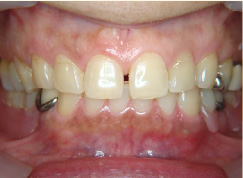

審美入れ歯

入れ歯は残っている歯に針金を引っ掛けるのが欠点。歯に負担をかけ見た目にも入れ歯と分かってしまう。針金を使わない入れ歯なら見た目だけではなく、歯にも負担が少ないですよ。

- 施術前

- 施術後